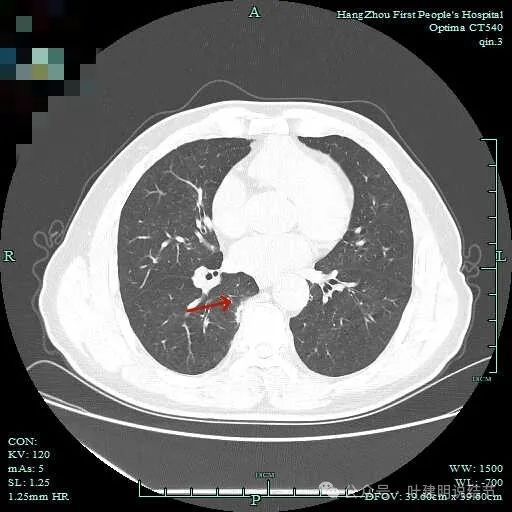

先看主病灶情况:

病灶出现,整体轮廓较清,胸膜略有牵拉。

密度不均匀,胸膜有轻微牵拉,边上有磨玻璃成分。

混合偏实性密度,瘤肺边界清,胸膜有牵拉。

表面不平,有小血管进入,整体轮廓与边界清。